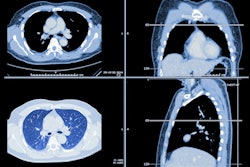

West Virginia University Hospitals has unveiled a fully mobile coach with an onboard CT scanner that will provide CT lung cancer screening in rural areas of West Virginia.

Called LUCAS (lung cancer screening), the mobile unit will serve patients from across the state with visits in the 42 West Virginia counties that don't have immediate access to lung cancer screening services. It can serve up to 20 patients a day.